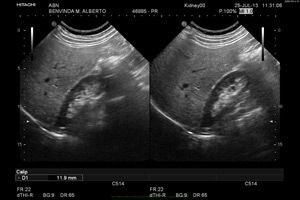

Ecografia

A ecografia é um método de diagnóstico por imagem usada para reproduzir imagens dos órgãos internos, tecidos, rede vascular e fluxo sanguíneo através do ultra-som.

O equipamento chamado de sonda envia ondas sonoras até á área a ser estudada, que as reflecte para o transdutor novamente e depois são convertidas em imagens bidimensionais. A captação dessas imagens são em tempo real, mostrando instantâneamente a posição dos órgãos internos e tecidos e o fluxo sanguíneo. A Ecografia é utilizada para o diagnóstico e acompanhamento de doenças e em procedimentos cirúrgicos.